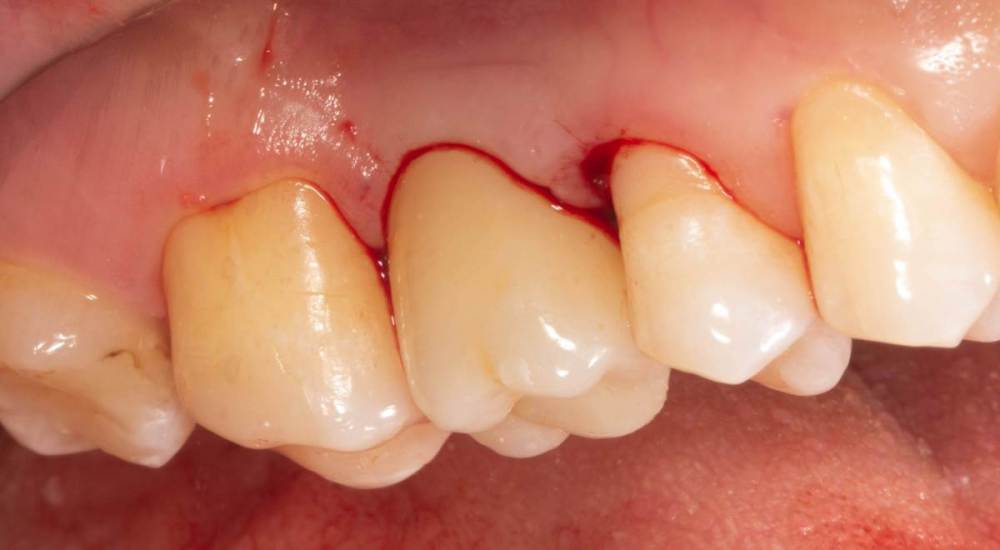

Женька Опубликовано 23 июля, 2022 Автор Поделиться Опубликовано 23 июля, 2022 (изменено) Кончилось вот так в общем. Сразу после фиксации. Коллеги, обойтись без разрезов на постоянных коронках можно только посредством временных? Изменено 23 июля, 2022 пользователем Женька 4 Ссылка на комментарий

Женька Опубликовано 23 июля, 2022 Автор Поделиться Опубликовано 23 июля, 2022 @Aquarius это винтовая фикса) разрезы потому что коронка намного шире формика у меня (конечно же попросил техника отдавить немного десну) Ссылка на комментарий